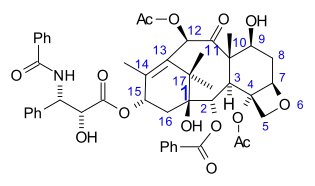

The nomenclature for paclitaxel is structured on a tetracyclic 17-atom skeleton. There are a total of 11 stereocenters. The active stereoisomer is (−)-paclitaxel (shown here).